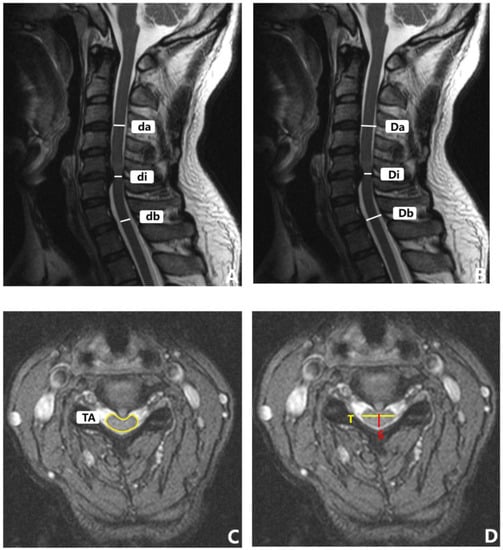

Figure 4.

Sagittal radiograph of cervical spine with representative measurements. (A) C2-C7 cobb angle (CL), T1 slope (T1S). (B) C2-7SVA.

Figure 5.

MRI parameter measurement of cervical spine. (A) MSCC. (B) MCC. (C) TA. (D) CR.